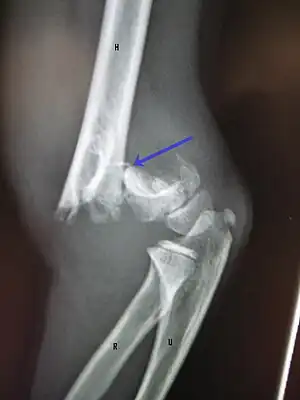

X-rays

Diagnosis is confirmed by x-ray imaging. Antero-posterior (AP) and lateral view of the elbow joint should be obtained. Any other sites of pain, deformity, or tenderness should warrant an X-ray for that area too. X-ray of the forearm (AP and lateral) should also be obtained for because of the common association of supracondylar fractures with the fractures of the forearm. Ideally, splintage should be used to immobilise the elbow at 20 to 30 degrees flexion in order to prevent further injury of the blood vessels and nerves while doing X-rays. Splinting of fracture site with full flexion or extension of the elbow is not recommended as it can stretch the blood vessels and nerves over the bone fragments or can cause impingement of these structures into the fracture site.[3]

On lateral view of the elbow, there are five radiological features should be looked for: tear drop sign, anterior humeral line, coronoid line, fish-tail sign, and fat pad sign/sail sign (anterior and posterior).[3][8]

Fish-tail sign - The distal fragment is rotated away from the proximal fragment, thus the sharp ends of the proximal fragment looks like a shape of a fish-tail.[8]